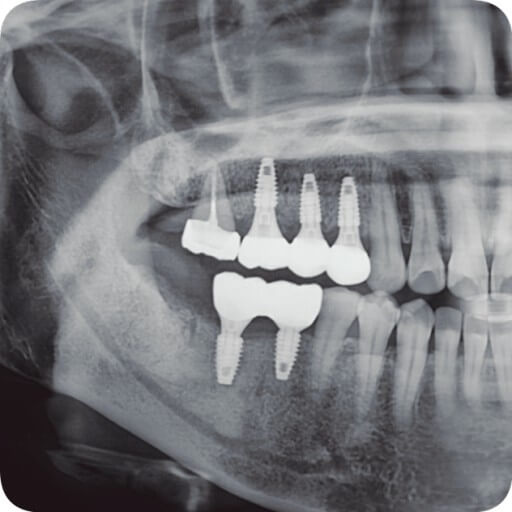

임플란트란?

임플란트는 쉽게 말씀드리면 치아를 제거한 부위에 인공적으로 만든 치아를 즉, 임플란트를 식립 하는 시술입니다.